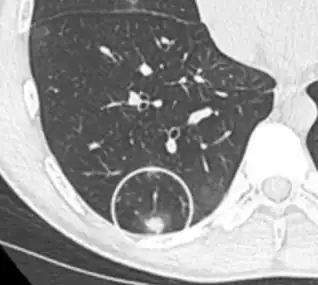

On chest X-ray and CT, pulmonary aspergillosis classically manifests as a halo sign, and later, an air crescent sign.[24] In hematologic patients with invasive aspergillosis, the galactomannan test can make the diagnosis in a noninvasive way. Galactomannan is a component of the fungal wall.[13] False-positive Aspergillus galactomannan tests have been found in patients on intravenous treatment with some antibiotics or fluids containing gluconate or citric acid such as some transfusion platelets, parenteral nutrition, or PlasmaLyte.[25][26]

Angioinvasive pulmonary aspergillosis

Angioinvasive pulmonary aspergillosis (closeup)